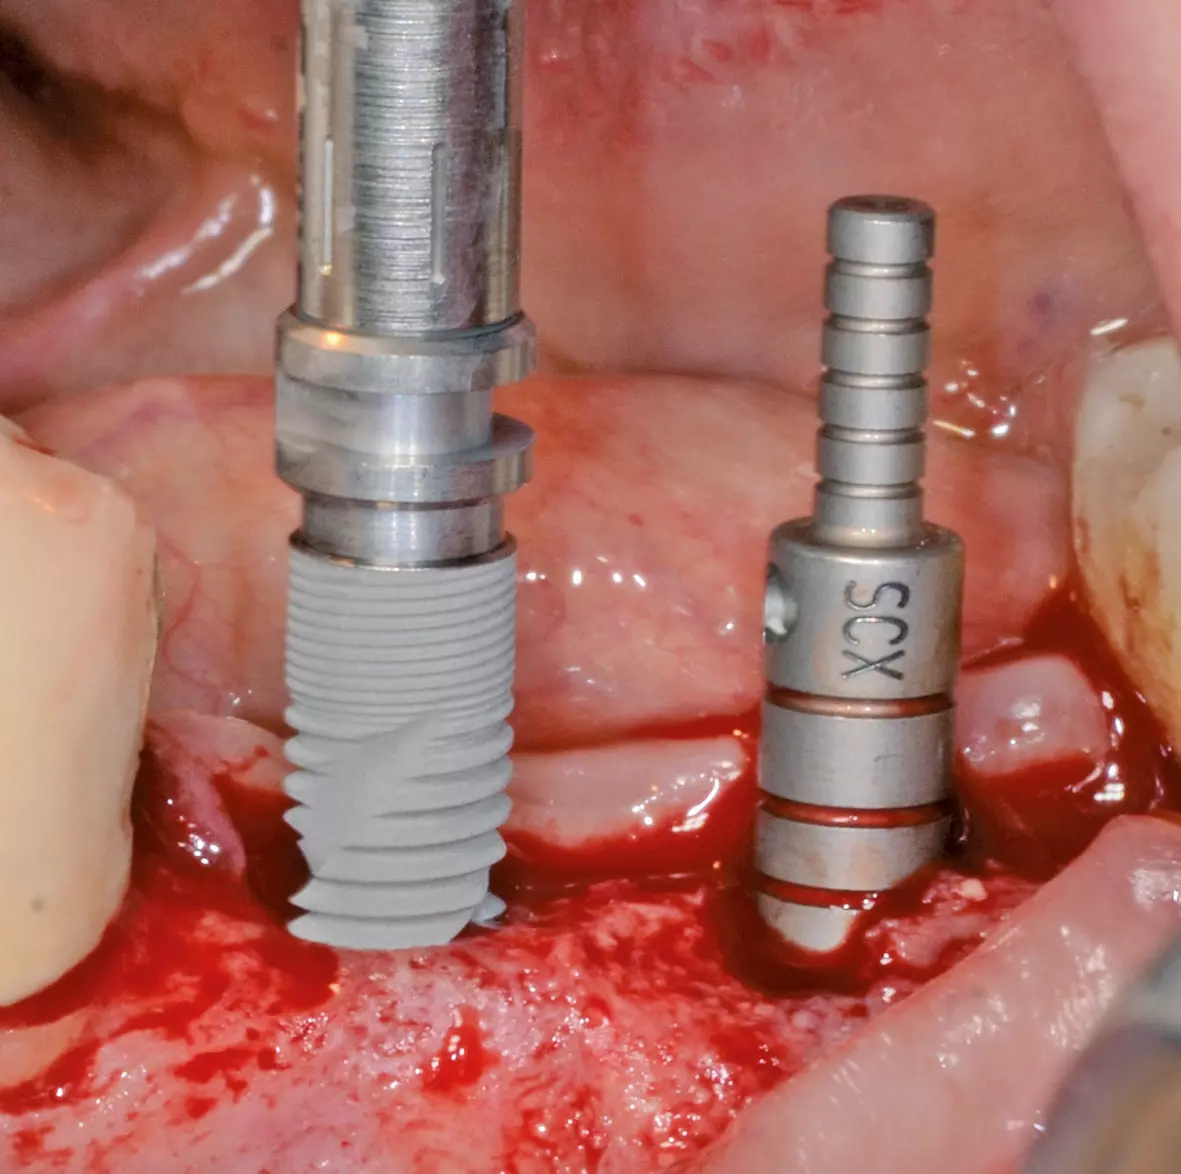

Die Implantation wurde ebenfalls in Lokalanästhesie und unter antibiotischer Abschirmung durchgeführt. Die Schnittführung orientierte sich an der vorhandenen Narbe mit leichter Tendenz nach lingual. Zur besseren Übersicht erfolgte die Präparation eines vestibulären und lingualen Mukoperiostlappens, bei dem zur Mobilisation und spannungsfreien Deckung eine Periostschlitzung durchgeführt wurde. Nach Ankörnung des Knochens, an den der Planung entsprechenden Stellen regio 35 und 36, wurde das Implantatbett, dem Bohrprotokoll des Herstellers folgend, aufbereitet (Abb. 5) und zwei Implantate (Bego SCX: regio 35: 4,1 x 10 mm; regio 36: 4,1 x 10 mm) primärstabil inseriert (Abb. 6). Zur vertikalen und lateralen Nachkonturierung des umgebenden Knochens wurden perioperativ gesammelte Knochenspäne, partikuläres xenogenes Knochenersatzmaterial (Geistlich BioOss) und präoperativ gewonnenes flüssiges PRF vermischt (Abb. 7) und anmodelliert (Abb. 8).